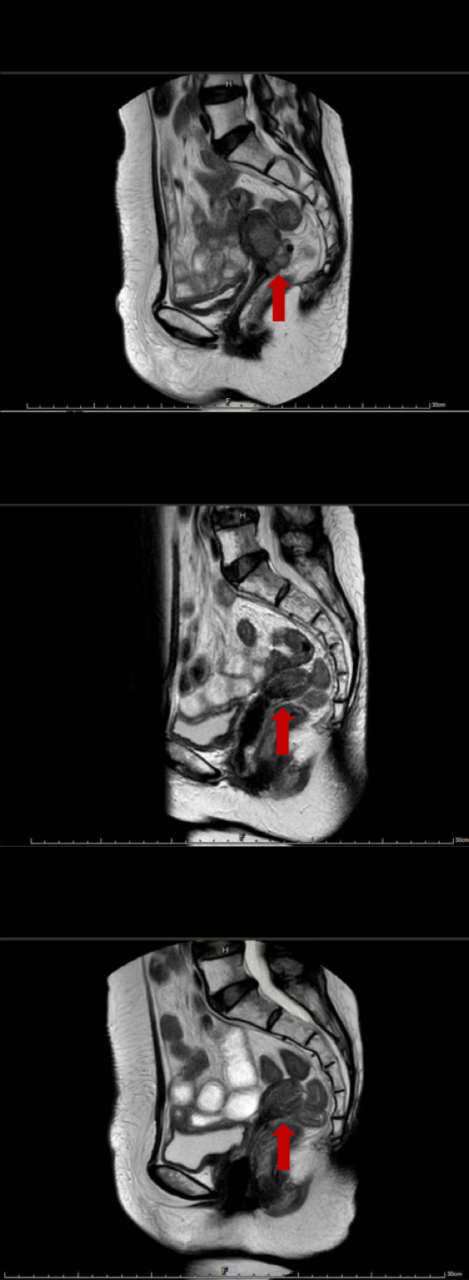

患者经过2个周期(2022年4月14日)治疗后,肿瘤退缩明显,疗效评价为部分缓解(PR);经过4个周期(2022年5月29日)治疗后,肿瘤消失,疗效评价为CR,并维持至今(最后一次疗效评价日期为2023年11月21日)。治疗期间的不良反应以骨髓抑制为主,多为1-2级,未造成治疗中断。患者于2023年5月10因腹部疼痛在外院就诊,并被诊断为胰腺炎,参考常见不良事件评价标准(CTCAE)5.0版,不良事件最高等级为3级,造成治疗中断。经乌司他丁及生长抑素治疗,于2023年5月24日缓解为1级,并于2023年5月31日恢复治疗。

患者影像资料: